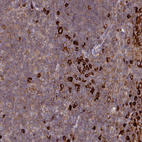

Immunohistochemical staining of human tonsil shows strong cytoplasmic positivity in subset of non-germinal center cells.